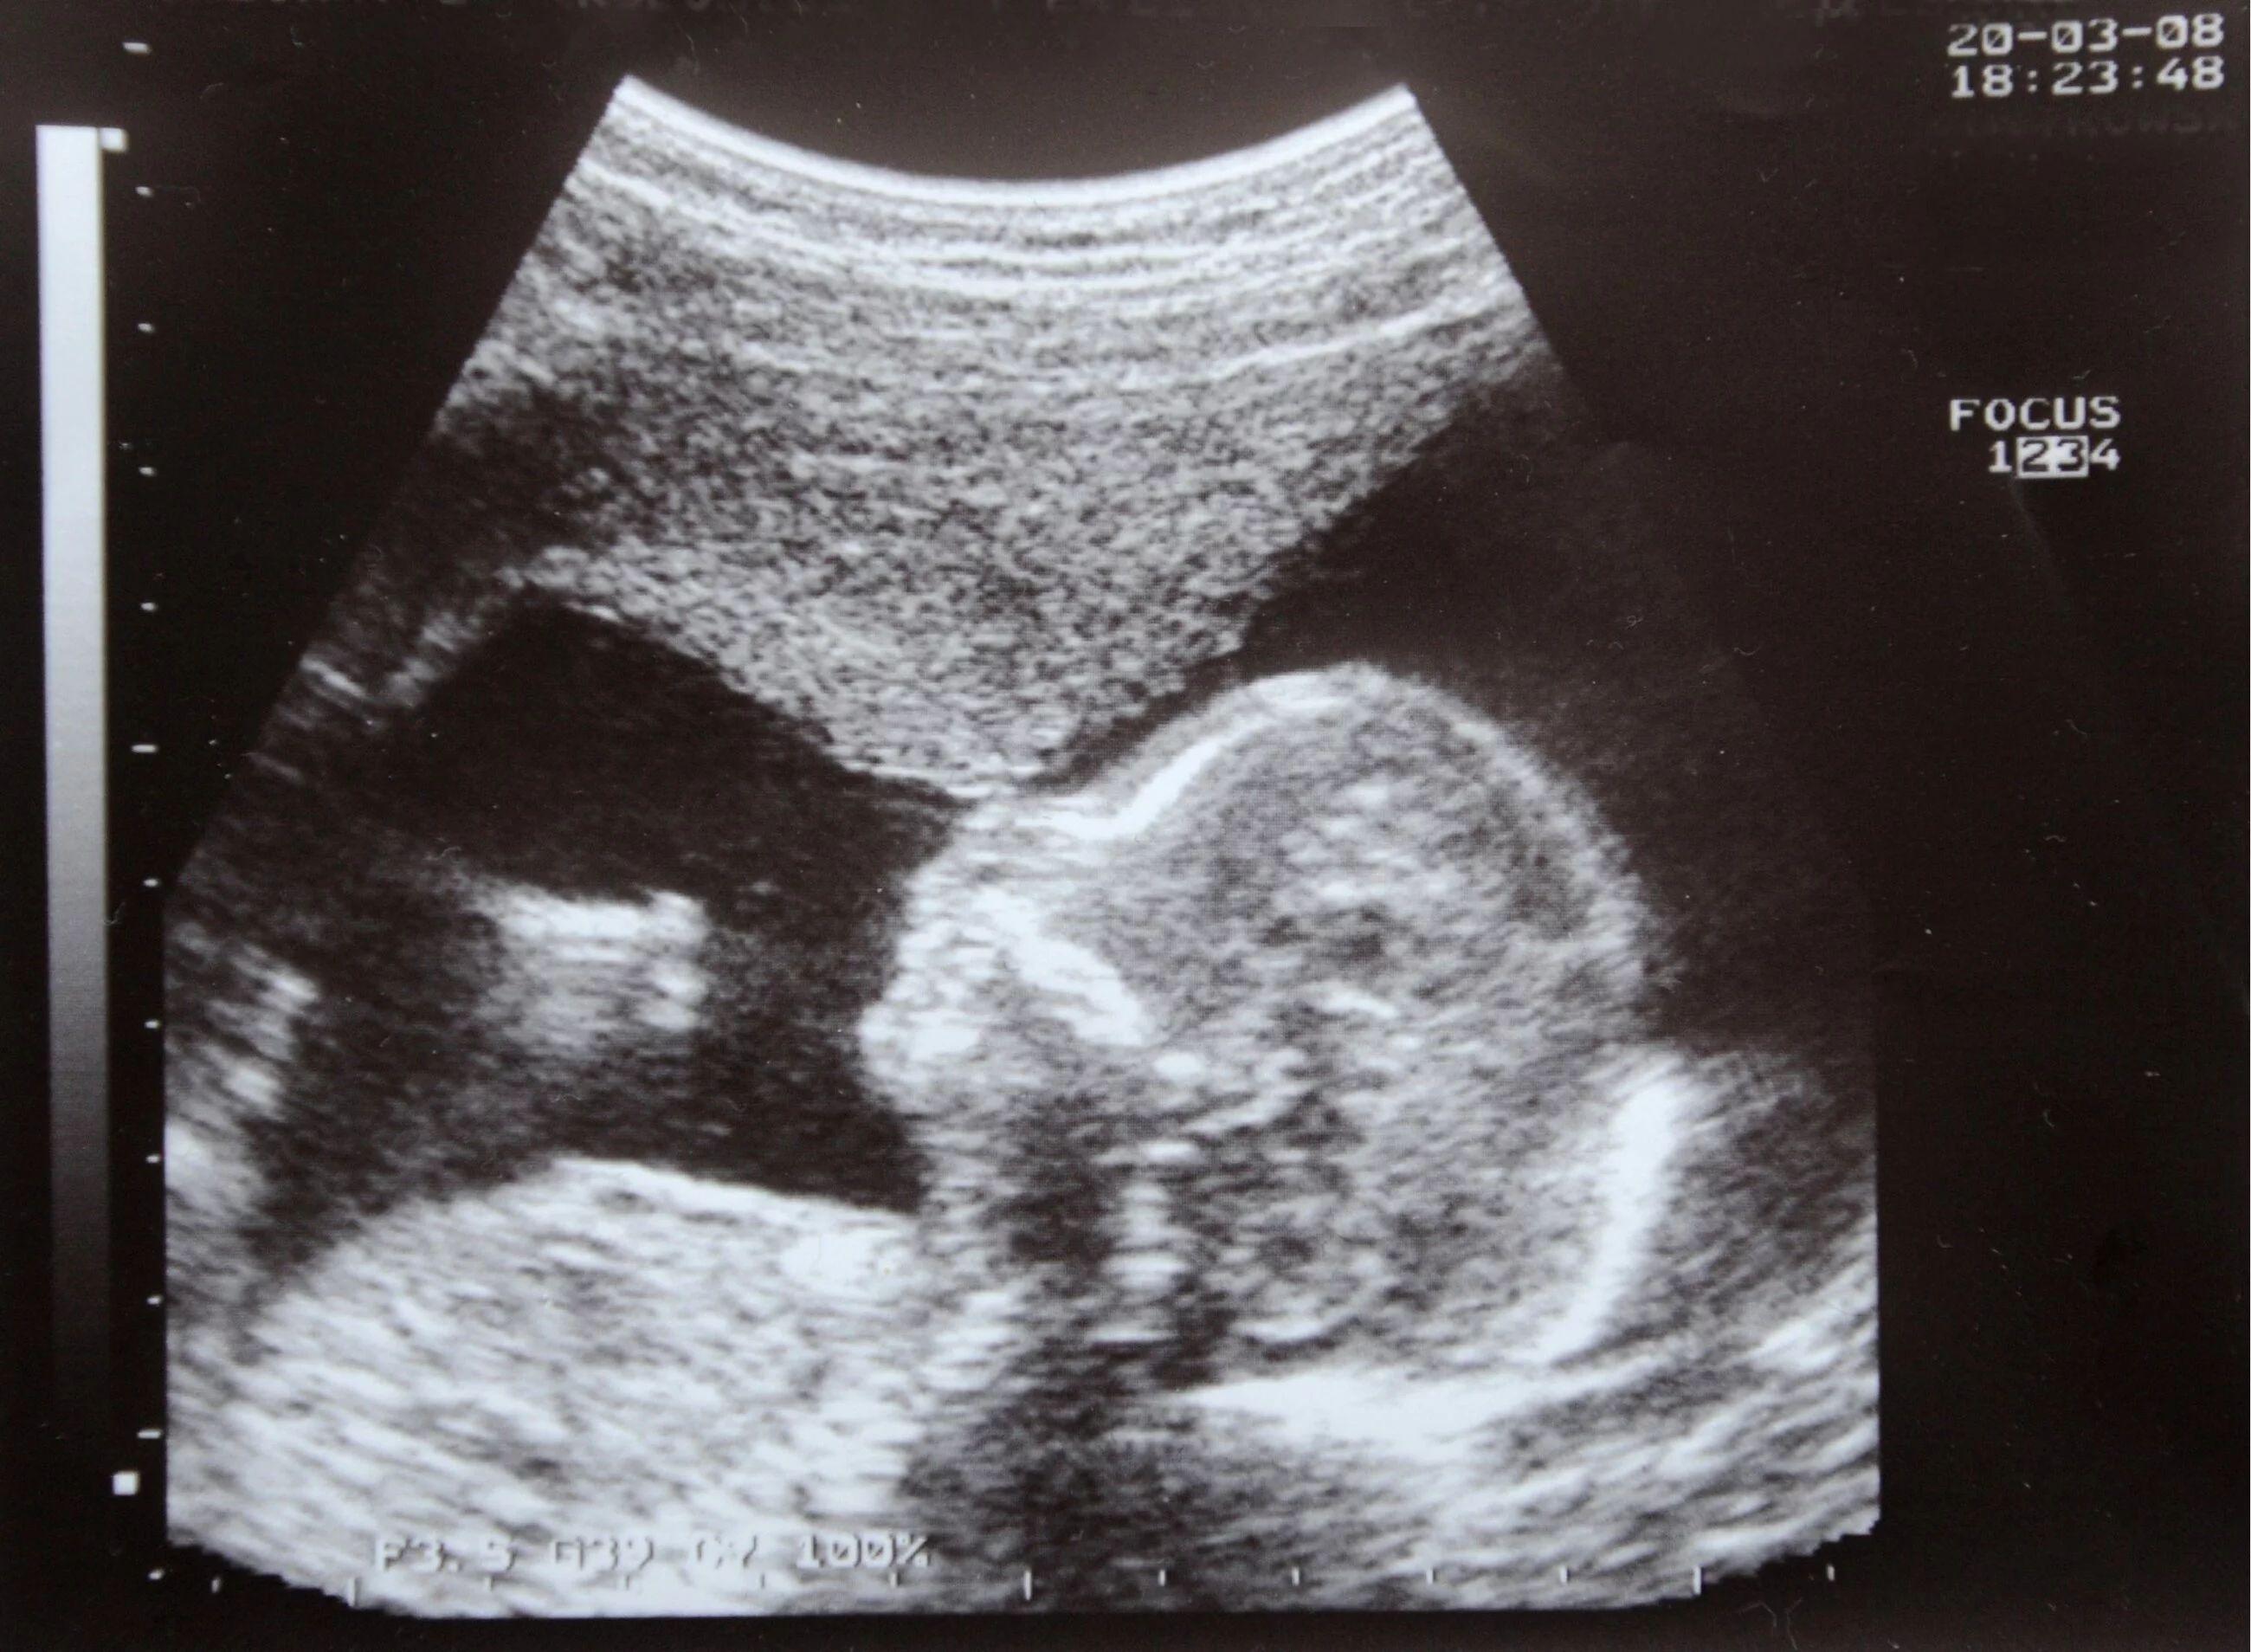

Każde życie ludzkie zaczyna się w momencie poczęcia w łonie matki i jest świętym darem Boga! „Ty bowiem utworzyłeś moje nerki, Ty utkałeś mnie w łonie mej matki. Dziękuję Ci, że mnie stworzyłeś tak cudownie, godne podziwu są Twoje dzieła” (Ps 139) – tak chwali twórcze dzieło Boga autor Psalmu 139. W tych słowach wyraża się wiara Ludu Bożego, na której opiera się antropologia biblijna. Święty Papież Jan Paweł II nazywa tę kwestię uwielbieniem Ewangelii Życia, która jest w centrum zbawczego orędzia Jezusa Chrystusa (Evangelium vitae, 83).

Apelujemy do przedstawicieli władz wszystkich szczebli! Zgodnie z art. 27 Konstytucji Ukrainy każdemu przysługuje niezbywalne prawo do życia. Nikt nie może być umyślnie pozbawiony życia. Według Słowa Bożego, a także badań naukowych, życie rozpoczyna się w momencie poczęcia! Chrońcie to PRAWO w stosunku do tych, którzy tego nie potrafią, w stosunku do najmniejszych spośród naszych obywateli, którzy rozpoczęli życie w łonie matki!